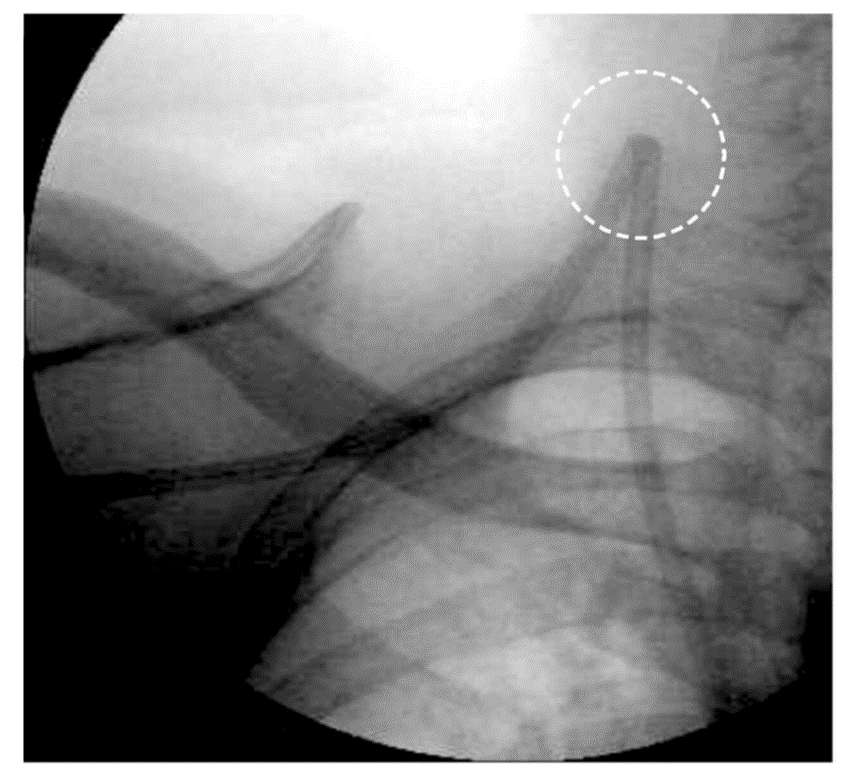

nمعیارهای بالینی وجود تنگی:

۱-  ترومبوز مکرر (دو مرتبه یا بیشتر در مدت یکماه)

۲- کانولاسیون مشکل (بعلت چسبندگی و تنگی)

۳- خونریزی طولانی مدت بعد از خارج نمودن کانول دیالیز (بعلت هیپرتانسیون وریدی)

۴- ادم قابل توجه اندام